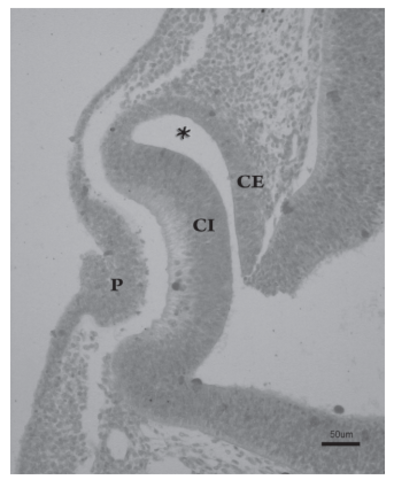

- Durante el día 32 del desarrollo, la placoda cristaliniana se invagina, hasta que un día más tarde se desprende de la superficie ectodérmica, formando la vesícula cristaliniana. Inicialmente ésta presenta una cavidad en su interior. Este fenómeno coincide con la aparición del cuerpo vítreo primario, entre la vesícula y la cúpula óptica.

Las fibras de la pared profunda de la vesícula cristaliniana se diferencian para formar las fibras primarias del cristalino, que se orientan anteroposterormente y son muy transparentes. De esta forma, se va obliterando la cavidad de la vesícula cristaliniana, hecho que ocurre al final de la séptima semana del desarrollo.

- Será ahora la vesícula cristaliniana la que induce la transformación del ectodermo de superficie dando lugar a la córnea, pero en su desarrollo también participarán células de otros orígenes. Así, el epitelio externo corneal es derivado del ectodermo de superficie, además las células derivadas de la cresta neural situadas alrededor de la cúpula óptica emigran y darán lugar al endotelio corneal.